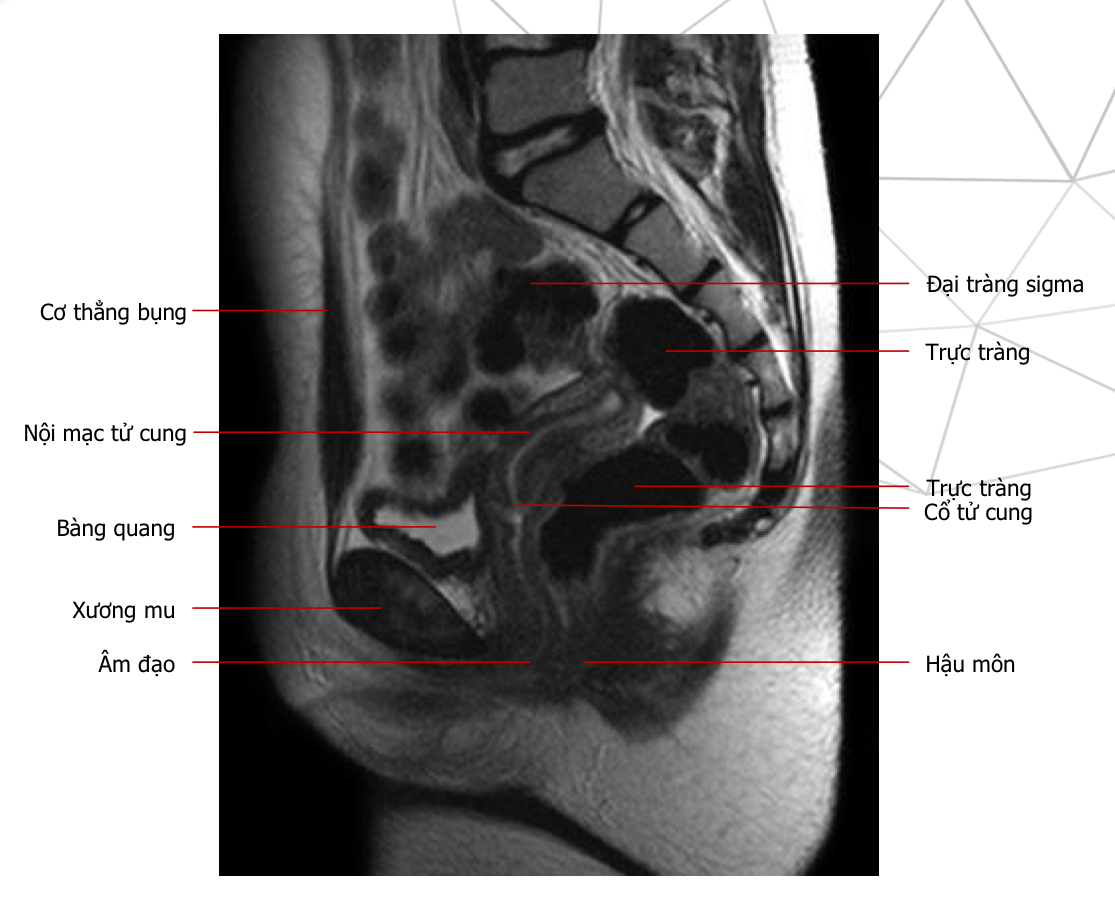

T2w sag, thì nghỉ

Tên chuỗi xung, mốc gp, thì

Mốc gp, chuỗi xung, thì

Thì nghỉ, T2w ax

chuỗi xung, thì, mốc gp

T2 cor, thì nghỉ